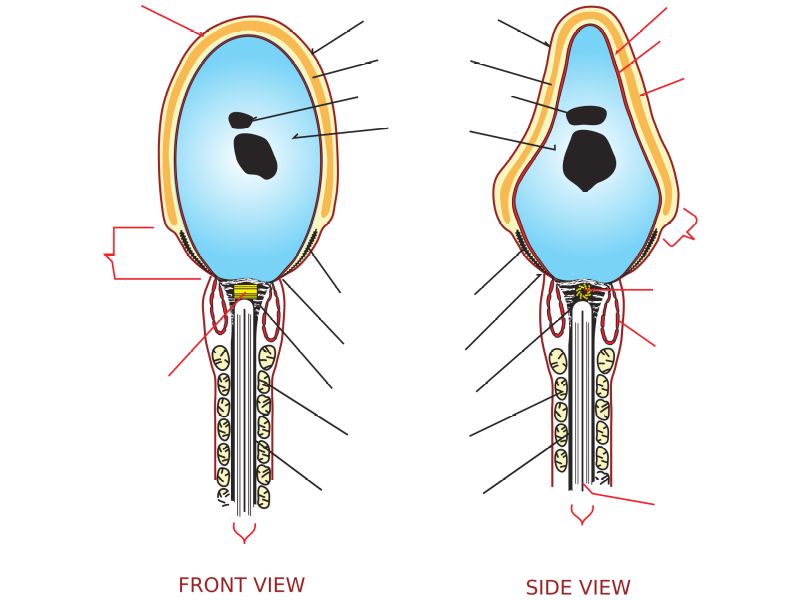

Spermatozoa

- Head

- Contains nucleus

- Dense chromatin

- Acrosomal cap anterior over nucleus

- Midpiece

- Mitochondrial sheath

- Small amount cytoplasm

- ATP for flagellar motility

- Tail

- Principle piece

- End piece

- Microtubuli for movement